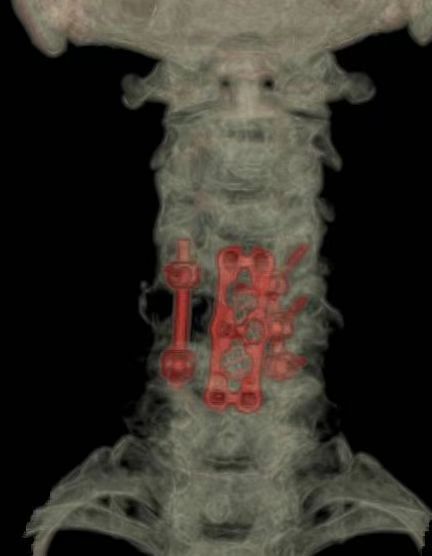

不仅如此,该院还探索即时3D打印重建“生命支柱”。肿瘤切除后留下的巨大缺损如何填补?该团队即刻运用先进的3D打印钛合金人工椎体,精准植入替代被切除的颈椎结构,并配合前路钉板系统进行坚强固定。这一创新重建方案,完美恢复了脊柱的力学支撑与稳定性。

值得一提的是,这台高难度手术的成功,是和祐医院骨科在脊柱肿瘤精准治疗领域深厚实力的体现。骨一科主任刘明表示,为高龄患者在颈椎高位实施肿瘤整块切除,本身就极具挑战性。此例患者的肿瘤还呈现180°包绕椎动脉和神经根的极端情况,大大增加了手术风险。手术的成功,得益于En-bloc整块切除技术、AI导航显微镜保障精准操作,以及个性化3D打印椎体的即时稳定重建,手术的成功都离不开多学科团队的紧密协作。